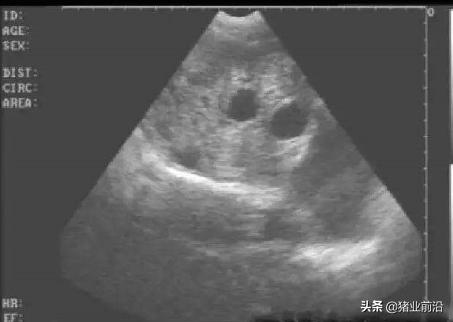

5、妊娠诊断

母猪配种后最早18-21天就可以通过妊娠诊断仪(B超)来测定母猪是否怀孕,最佳的测孕时间是配种后28-35天,此时孕囊最容易观察,同时也可以通过观察母猪是否出现返情来判断配种是否成功。